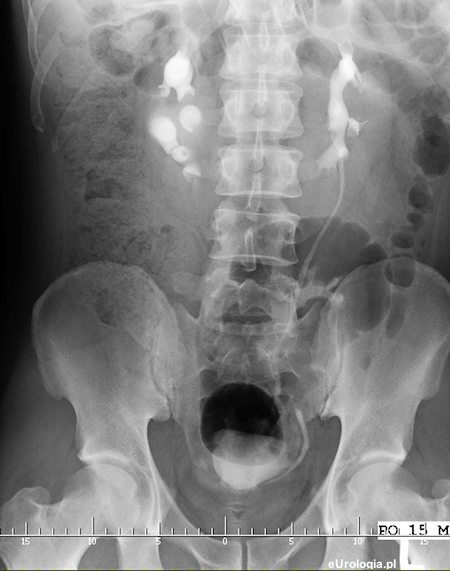

Fot. Nerka podkowiasta - obraz w urografii.